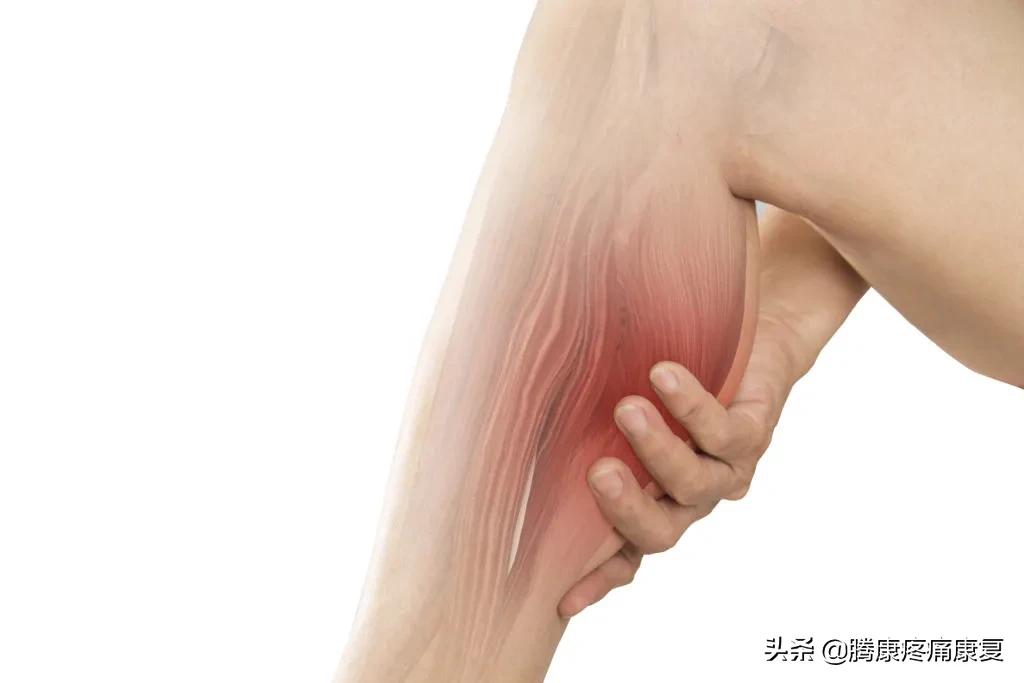

小腿肌肉痉挛

小腿肌肉痉挛是指一块或多块小腿肌肉突然、不自主地收缩,这种现象被称为腿部痉挛(charley horses)

大约60%的成年人在夜间体验过腿部抽筋,平均每次持续9分钟,之后,小腿肌肉可能会疼上好几天。

小腿肌肉抽筋会非常紧张和疼痛,甚至会有明显的结或抽搐感。但我们仍不清楚是什么原因导致了这些问题:

- 小腿抽筋可能与高强度运动后的肌肉疲劳有关。

腓肠肌内侧拉伤

腓肠肌内侧拉伤是小腿肌肉突然过度拉伸时发生的急性损伤,这会导致小腿肌肉纤维出现小撕裂。

腓肠肌拉伤通常发生在涉及短跑或跳跃的运动或锻炼活动中,这是小腿肌肉劳损最常见的类型之一。

有些人在受伤时会听到“砰”的一声,此时你可能感觉不到疼痛,然后在走了几步之后,疼痛就开始了,它可以被描述为一种尖锐或撕裂的感觉。

如果拉伤严重,可能会出现肿胀和瘀伤。在某些情况下,疼痛可能因为过于剧烈而无法行走。